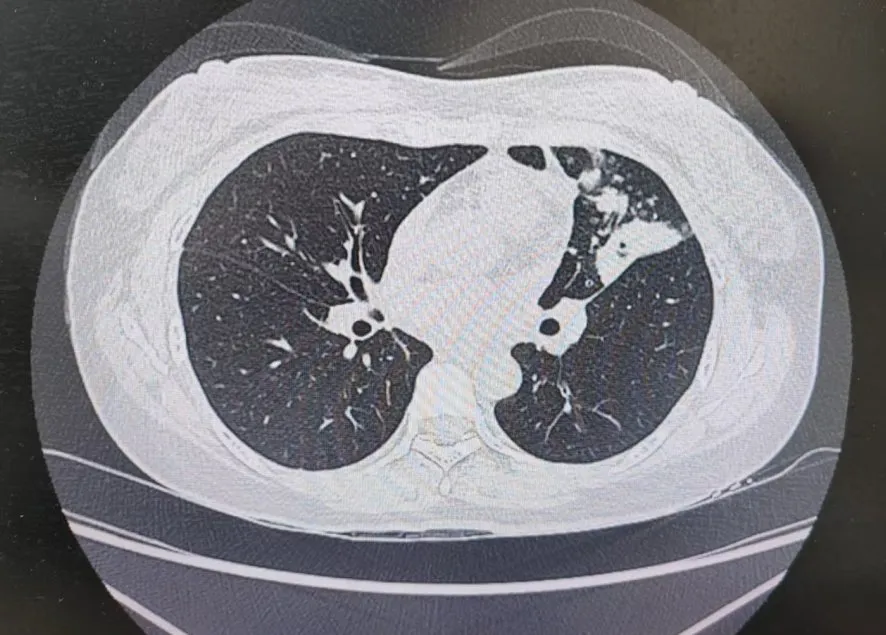

患者肺部CT影像

“一般來說,肺炎經(jīng)過一周的抗感染治療,病灶會有所吸收。但陳女士的肺部陰影紋絲不動,這種情況必須提高警惕。”宋剛主任團隊立即啟動了更深入的“三部精準診斷”程序:

3、CT引導(dǎo)下穿刺活檢:病理診斷為左肺上葉腺癌。

肺炎型肺癌,因其影像學(xué)表現(xiàn)與普通肺炎極為相似,臨床上誤診率極高。然而確診僅是第一步。宋剛主任當天即召集腫瘤科、病理科、影像科等多學(xué)科專家會診,為陳女士制定個體化治療方案。